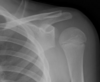

Anterior vs posterior shoulder dislocation on XR

Anterior shoulder dislocation

Posterior shoulder dislocation